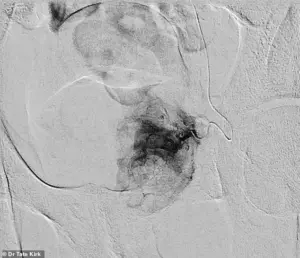

The process involves inserting a catheter into the artery supplying blood to the prostate, followed by the injection of tiny particles that block blood flow to the affected tissue.

Pre-embolization imaging reveals the artery’s full vascular supply, while post-embolization scans show the complete cessation of blood flow to the prostate, effectively reducing its size and alleviating symptoms.